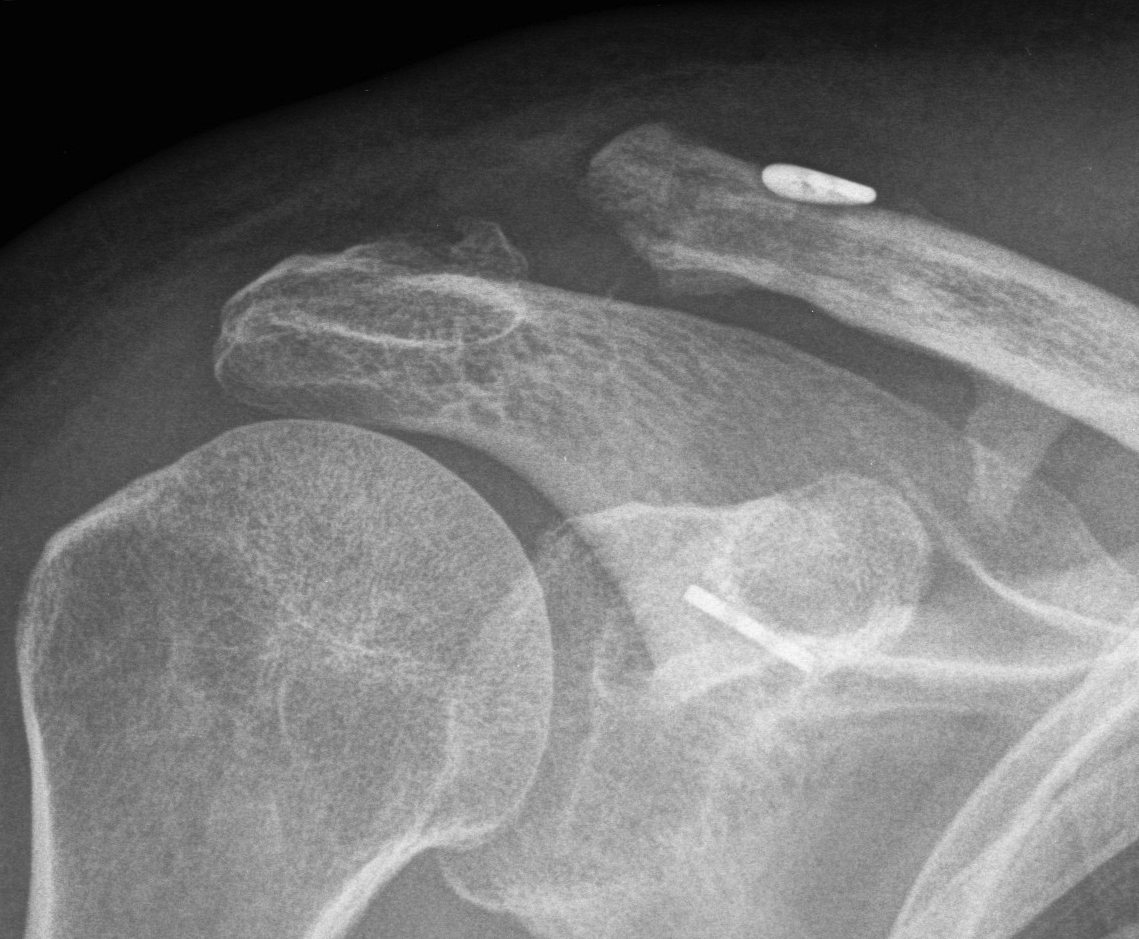

IV AC and CC ligaments disrupted and clavicle displaced posteriorly into trapezius

- can be easily missed

- need axillary lateral